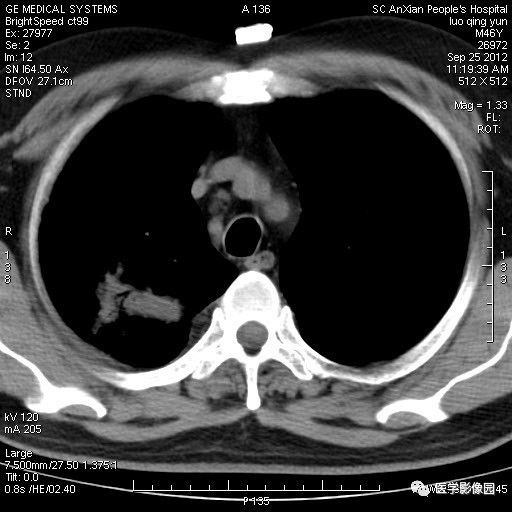

影像学表现:右上肺见不规则团块状高密度阴影,略有分叶级毛刺,边缘模糊,邻近胸膜增厚,增强扫描呈轻中度强化。

诊断结果:右上肺炎性假瘤

本病影像学表现无绝对特征性。单发多见,多位于肺表浅部位,多呈圆形或椭圆形,直径多在2-5cm或更大;多有假包膜,边缘多清晰光整,有时也毛糙,并可有分叶或毛刺;邻近胸膜局限性增厚、牵拉,病灶边缘呈桃尖样突起即桃尖征(尖端指向胸膜);增强扫描多呈中度均匀强化,持续时间较长。亦可显著强化。